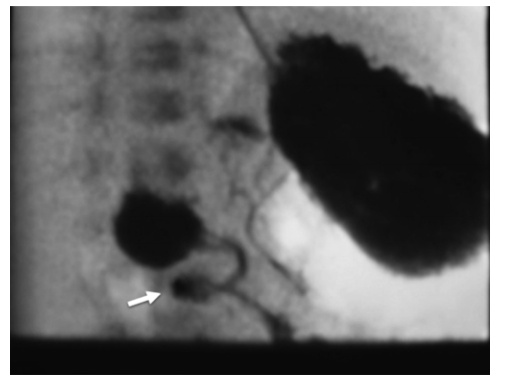

Volvulus

The clinical presentation of acute midgut volvulus includes:

Occurrence in the first decade of life

Sudden onset bilious vomiting

Diffuse abdominal pain out of proportion to physical exam

Chronic midgut volvulus typically presents with recurrent abdominal pain and intestinal malabsorption.

corkscrew appearance (white arrow)

PE, Diagnosis, Treatment

Some degree of abdominal distention should be seen on physical examination.

The gold standard for diagnosing intestinal malrotation is an upper gastrointestinal series. Ultrasound imaging is also associated with a 0% false positive rate in the hands of an experienced user.

Intestinal congenital defects, such as malrotation, require surgical correction. The most effective procedure done for malrotation is the Ladd procedure which involves a reduction of the volvulus (if present), division of the mesenteric bands, placing the small bowel on the right, the large bowel on the left of the abdomen, and an appendectomy.